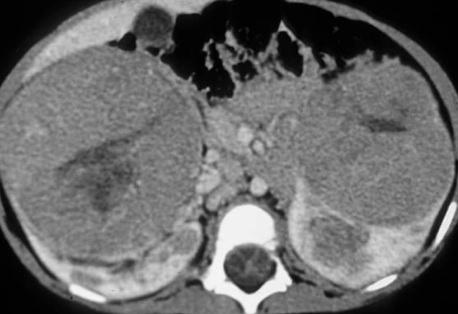

The next best step in management of this child with bilateral renal masses is